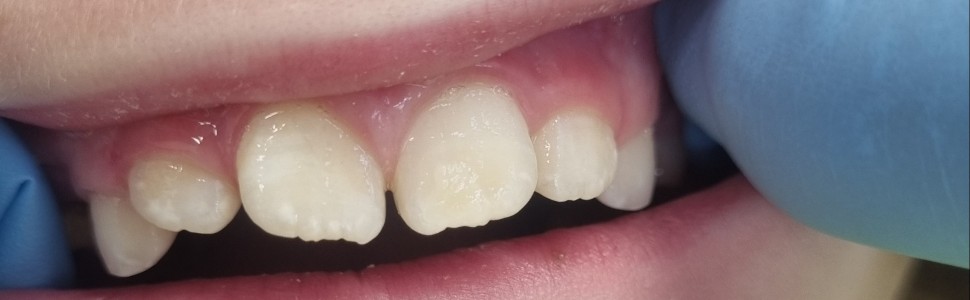

Hipomineralizacja trzonowcowo-siekaczowa jest jakościowym zaburzeniem rozwojowym szkliwa spowodowanym przez czynniki ogólnoustrojowe zaburzające amelogenezę. Klinicznie choroba manifestuje się m.in. obecnością dobrze odgraniczonych biało-żółto-kremowo-brązowych zmętnień szkliwa. Jedną z metod leczenia przednich zębów z MIH jest infiltracja. Ten zabieg ma na celu wypełnienie żywicą porowatych przestrzeni międzypryzmatycznych, zablokowanie penetracji bakterii i zatrzymanie dalszej utraty minerałów. Żywica infiltranta zmniejsza rozpraszanie światła pomiędzy kryształami szkliwa, co pozwala na poprawę estetyki zębów dotkniętych MIH. Efekt leczenia metodą infiltracji jest nieprzewidywalny, bo stopień infiltracji żywicy zależy od głębokości i rozległości hipomineralizacji szkliwa. W pracy przedstawiono leczenie MIH na zębach siecznych szczęki metodą infiltracji.

Molar-incisor hypomineralization is a qualitative developmental disorder of enamel caused by systemic factors that disturb amelogenesis. Clinically, the disease manifests itself, among others, by the presence of well-demarcated white-yellow-cream-brown enamel opacities. One of the methods of treating anterior teeth with MIH is infiltration. This procedure aims to fill the porous interprismatic spaces with resin, block the penetration of bacteria and stop further mineral loss. The infiltrant resin reduces the scattering of light between enamel crystals, which allows for improving the aesthetics of teeth affected by MIH. The effect of treatment with the infiltration method is unpredictable, because the degree of resin infiltration depends on the depth and extent of enamel hypomineralization. This paper presents the treatment of MIH using the infiltration method on maxillary incisors.